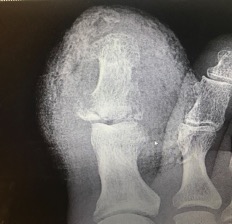

X-Rays on admission revealed a fracture of the medial base of the first distal phalanx. Erosive changes at the lateral distal phalanx and the distal aspect of the proximal phalanx suggested potential osteomyelitis. Blood and deep tissue cultures showed methicillin-susceptible Staphylococcus aureus (MSSA).

During surgery, the distal aspect of the hallux had a typical presentation for cellulitis and osteomyelitis. After disarticulating the metatarsophalangeal joint, the remaining soft tissue was healthy and viable in appearance. The head of the first metatarsal and the base of the proximal phalanx, however had signs of osteoarthritis and a blue/gray discoloration. Morphology was otherwise normal.

The team considered resecting the distal first metatarsal but ultimately decided against it due to the normal consistency of the bone and surrounding soft tissue. We sent a sample of the proximal phalanx that was also discolored to pathology along with the distal hallux for analysis. The patient followed up at the podiatry clinic and his surgical site completely healed in four weeks.

The pathology report described sections of bone that were gray-blue-tan with smooth articular surfaces. The distal phalanx and interphalangeal joint had devitalized bone with marrow space fibrosis and scattered lymphocytes consistent with osteomyelitis.